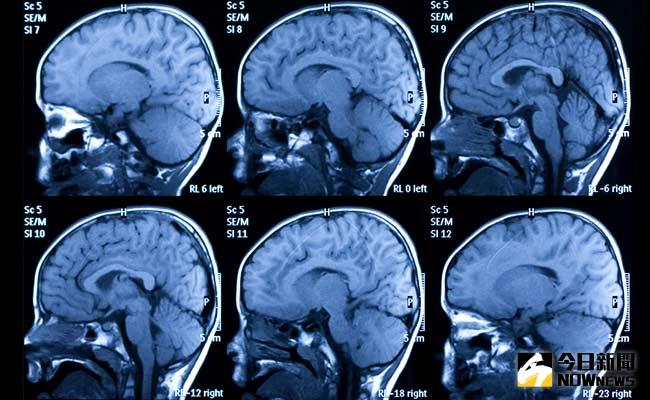

「 解離性人格症(Dissociative identity disorder)」,其實就是大家熟悉的多重人格(Multiple personality disorder),這邊則稱為DID。早年被稱為「歇斯底里症」,被認為是種身體上的疾病,因為Hysteria(歇斯底里)為希臘文「子宮」的意思,希臘人認為該症的發生,乃是因為女人的子宮在體內遊走所致,必須將其歸回定位才能痊癒。到了中古時代,隨著宗教觀念的影響,該症又被解釋成與魔鬼、巫術有關(也就是所謂的附身啦!當然這又牽扯到靈魂附體或驅魔,這邊哺哺先不詳述)。直到十七世紀後,Hysteria才被視為心理上的疾病,而十九世紀則開始有人利用催眠來治療該症。

患者通常有兩個以上的獨立人格(如只有兩種人格則被稱為:雙重人格),所謂的解離是一種心理防衛機制,當我們受到極大的壓力或是創傷後,有的人會大哭、捶牆壁或者一言不發,而DID患者為了保護自己,會自發性的排除於意識之外(通常也好發於幼年,也就是無從對抗外力的年紀),這種解離機制原是為了保護主體,而解離性患者很有可能會覺得自己在跟自己對話(而被誤認為是精神分裂症),甚至像電影中因應各種環境而延伸出的對應人格。